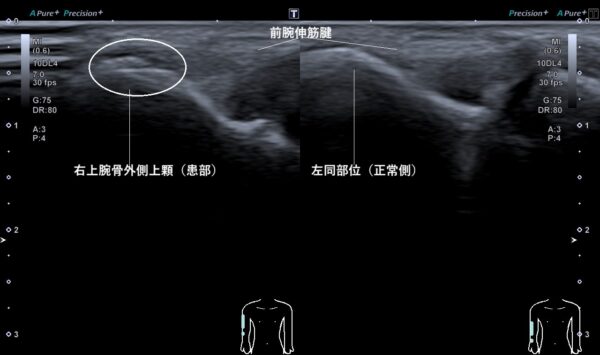

それらの所見から、上腕骨外側上顆を超音波画像検査してみると骨の表面が剥離していました(画像、丸の中の白い線が重なっている箇所)。

なお、骨の表面の剥離は骨折ではありませんが、骨癒合(骨がくっつくこと)が必要であるため、施術では骨折の際に使用する治療機器を使用します。